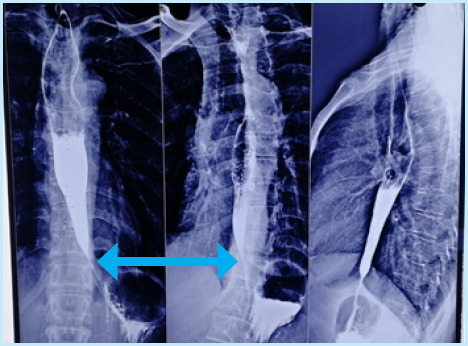

摘要:贲门失弛缓症是一种影响下食道括约肌和食道体的罕见疾病。由于其症状广泛,因此很难诊断。在此,我们报告了 9 个月内的三例贲门失弛缓症病例。第一例患者是一名 18 岁的男性,出现吞咽困难,经过吞钡和高分辨率测压(HRM)检查发现患有贲门失弛缓症。第二例患者是一名 37 岁的女性,由于患有多种并发症,诊断过程漫长,最终在吞钡检查中发现了贲门失弛缓症。第三例患者是一名 47 岁的女性,在吞钡检查中被迅速确诊。所有病例均通过腹腔镜海勒氏肌切开术和前路多氏胃底折叠术获得成功治疗。本系列病例强调了延误诊断的可能性,以及早期识别、有针对性的诊断方法和手术治疗效果的重要性。

Abstract: Achalasia cardia is a rare disorder that impacts the lower esophageal sphincter and esophageal body. Due to its wide range of symptoms, it can be difficult to diagnose. Here we report three cases of Achalasia Cardia during a period of 9 months. The first patient, an 18-year-old male, presented with dysphagia and was evaluated with barium swallow and high-resolution manometry (HRM) revealing Achalasia Cardia. In the second case, a 37-year-old female had a prolonged diagnostic journey due to multiple comorbidities before a barium swallow finally revealed achalasia cardia. The third patient, a 47-year-old female was promptly diagnosed with barium swallow. All the cases were successfully treated with laparoscopic Heller's myotomy with anterior Dor's fundoplication. This case series highlights the potential for delayed diagnosis and the importance of early recognition, tailored diagnostic approaches, and the efficacy of surgical management.